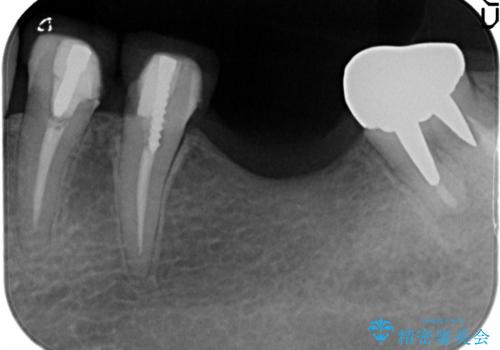

- 左下6番目の歯が欠損しており、インプラントで治療することとなりました。

骨の横幅が薄くなっており、インプラントを埋入するには骨幅が足りない状態でした。

まず最初に骨造成を行い、その後にインプラント埋入手術を行うこととなりました。

骨を増やすための手術が必要になるので、通常のインプラント治療より手術回数が一回多くなってしまうのがデメリットですが、将来的に安定したインプラントにするため、骨造成手術を前もって行いました。

しっかりとした骨幅を獲得し、理想的な太さのインプラントを埋入することができました。